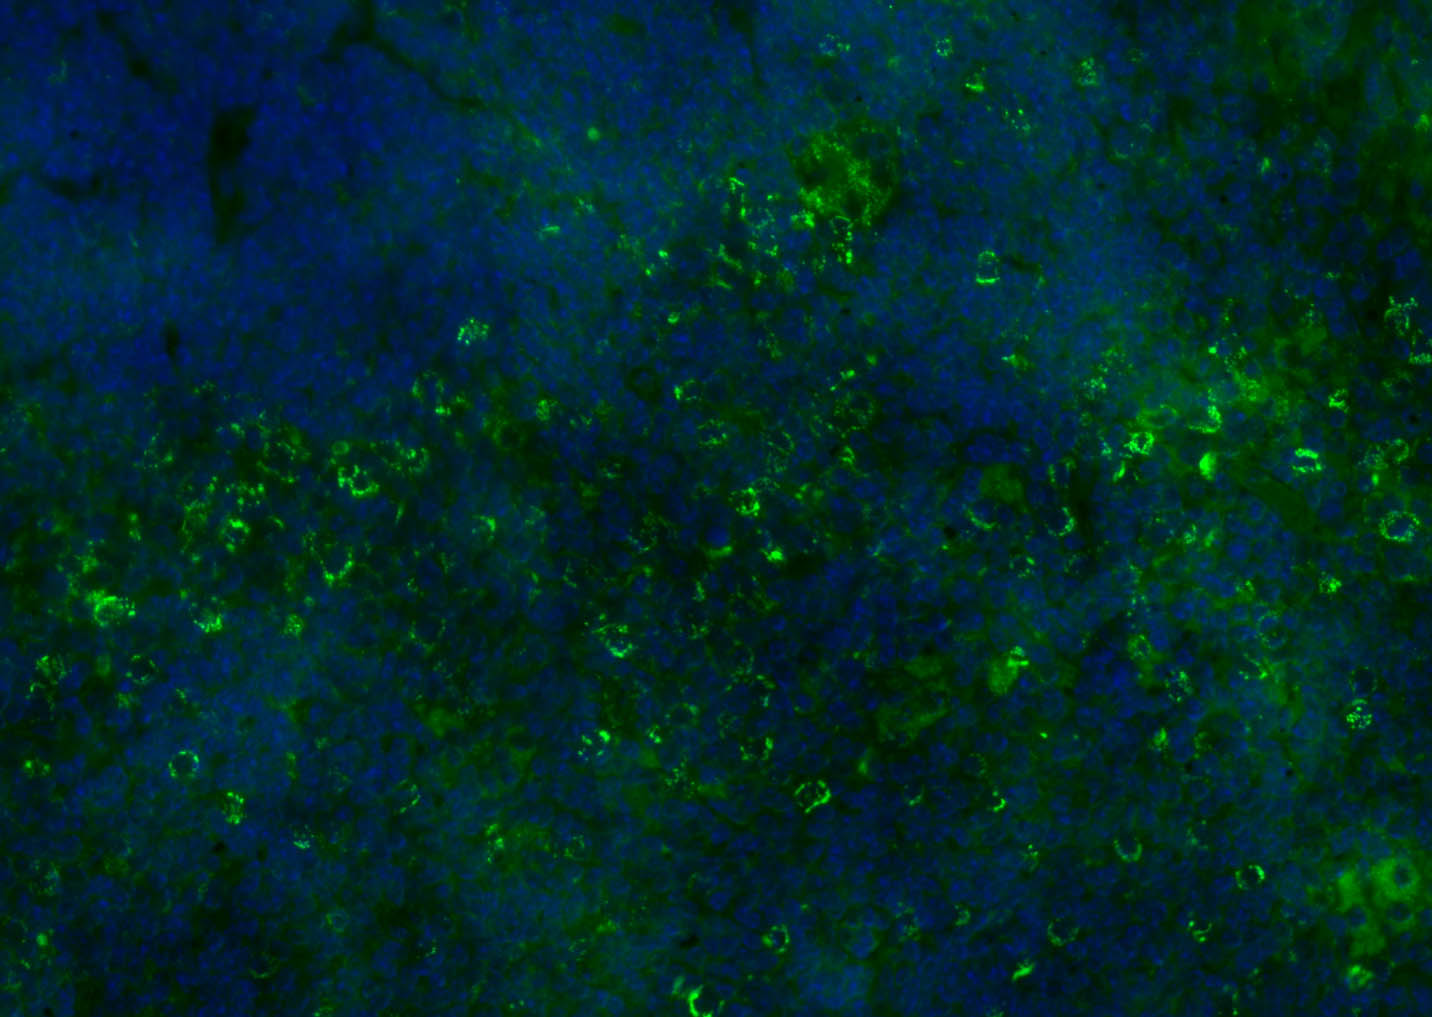

Paraformaldehyde-fixed, paraffin embedded (mouse spleen); Antigen retrieval by boiling in sodium citrate buffer (pH6.0) for 15min; Blocking buffer (normal goat serum) at 37°C for 30min; Antibody incubation with (CD8B) Polyclonal Antibody, Unconjugated (bs-4914R) at 1:200 overnight at 4°C, followed by a conjugated Goat Anti-Rabbit IgG antibody (bs-0295G-FITC) for 90 minutes, and DAPI for nuclei staining.